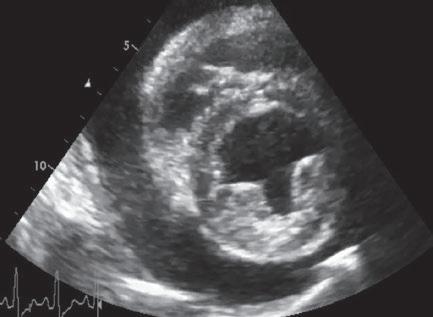

Para realizar la mayoría de los procedimientos quirúrgicos, es imprescindible disponer de un equipo de fluoroscopia, que permite la adquisición rápida de

La radiología intervencionista se realiza mediante un abordaje guiado por distintas técnicas de imagen como, por ejemplo, la ecografía, la fluoroscopia o la tomografía computarizada, para alcanzar la zona a diagnosticar o tratar.

La radiología intervencionista, también conocida como radiología vascular e intervencionista, es una especialidad que se encarga del diagnóstico y tratamiento de una gran cantidad de enfermedades de una manera mínimamente invasiva. Se realiza mediante un abordaje guiado por distintas técnicas de imagen como, por ejemplo, la ecografía, la fluoroscopia o la tomografía computarizada, para alcanzar la zona a diagnosticar o tratar.

La radiología vascular e intervencionista ofrece una alternativa segura y eficaz a la cirugía en muchas enfermedades. Entre sus ventajas para el paciente destaca una menor agresión a nivel tisular, una rápida recuperación, procedimientos sin dolor, rápidos y seguros, un menor coste respecto a otras muchas cirugías con mis-

imágenes basadas en rayos X y posteriormente las convierte en una señal de vídeo en tiempo real. Estas imágenes pueden manipularse ofreciendo funciones como la angiografía de sustracción digital, mapeo vascular y ampliación. Respecto a una radiografía, la exposición de rayos X necesaria para realizar una fluoroscopia es baja, pero debido a la duración de las series de imágenes que habitualmente se toman, el nivel de exposición en los pacientes suele ser elevado. Por lo tanto, es importante controlar el tiempo de exposición y llevar un registro de este. El fluoroscopio debe estar situado en una sala adecuada para su uso seguro, y todo el personal que entre en la sala de fluoroscopia debe protegerse de la radiación utilizando un delantal plomado, protectores de tiroides y gafas plomadas.